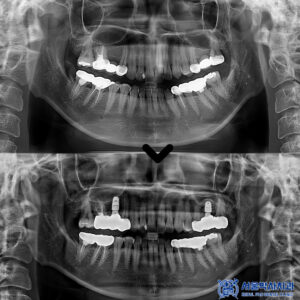

신흥동치과, 음식 씹을 때 아파요 (재신경치료 및 임플란트로 치료)

신흥동치과, 음식 씹을 때 아파요 (재신경치료 및 임플란트로 치료) 안녕하세요. 신흥동치과 서울박사치과입니다. 치아 신경치료는 치아를 살리기 위한 마지막 수단으로 불릴 만큼 중요한 치료인데요. 특히 재신경치료의 경우 처음 신경치료가 제대로 되지 않았거나 이후 문제가 생겼을 때 다시 진행하는 치료로, 일반적인 신경치료에 비해 난이도가 높고 의료진의 섬세한 손기술과 경험이 요구됩니다. 오늘은 더보기…